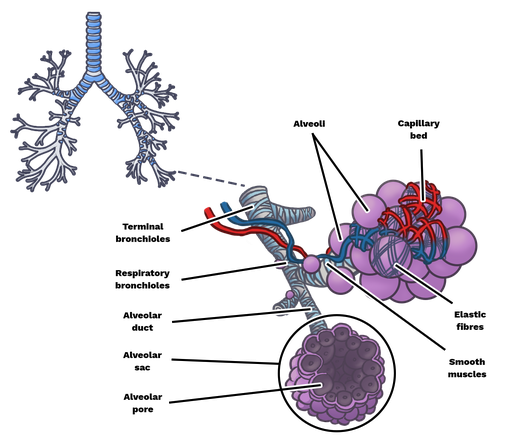

6. Alveolus

Alveolus merupakan struktur berbentuk bola-bola mungil atau gelembung paru-paru yang diliputi oleh pembuluh-pembuluh darah. Epitel pipih yang melapisi alveoli memudahkan darah di dalam kapiler-kapiler darah mengikat oksigen dari udara dalam rongga alveolus.

Pertukaran udara yang sebenarnya terjadi di alveoli. Dalam paru-paru orang dewasa terdapat sekitar 300 juta alveoli, dengan luas permukaan sekitar 160 meter per segi atau sekitar 1 kali luas lapangan tenis, atau luas 100 kali dari kulit kita.

Paru-paru kanan memiliki tiga lobus, sehingga lebih besar dari paru-paru kiri yang terdiri dari dua lobus. Paru-paru dibungkus oleh dua lapis selaput paru-paru atau pleura. Di bagian dalam paru-paru terdapat gelembung halus yang merupakan perluasan permukaan paru-paru yang disebut alveolus, dan jumlahnya ± 300 juta buah. Luas permukaan alveolus diperkirakan mencapai 160 m² atau 100 kali lebih luas daripada luas permukaan tubuh.